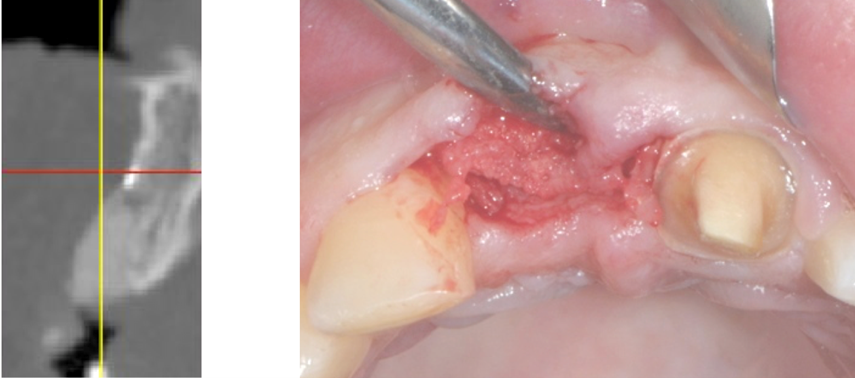

Immagine clinica e radiografica al momento della rimozione della membrana

Inserimento implantare dopo quattro mesi